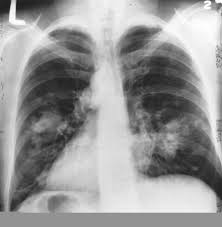

X-ray of lungs

Lung cancer is the primary cause of cancer death in the United States, and the leading cause of lung cancer is also the most preventable, smoking cigarettes. While the most important thing that you can do prevent lung cancer is quit smoking, a new study by the John Hopkins Bloomberg School of Public Health finds that a diet rich in fruit, particularly tomatoes and apples, may slow lung function decline in ex-smokers.